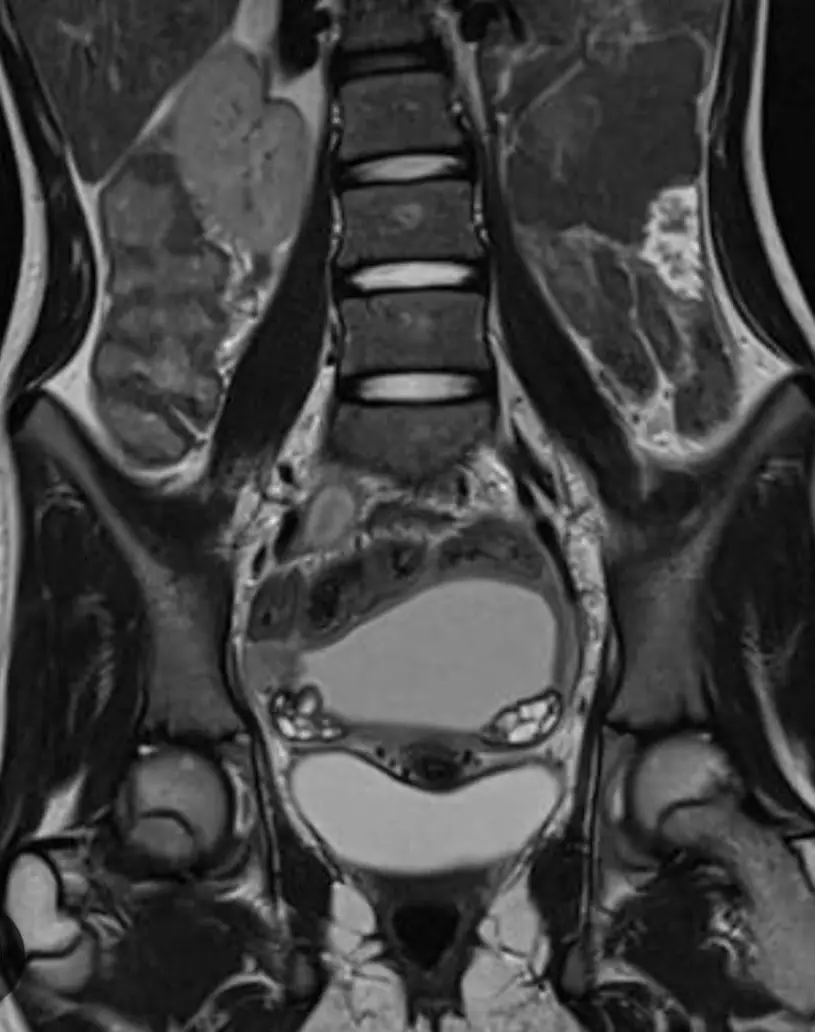

МРТ малого таза у женщин

Визуализация матки, яичников, маточных труб, влагалища, лимфоузлов, параметральных вен, прямой кишки.